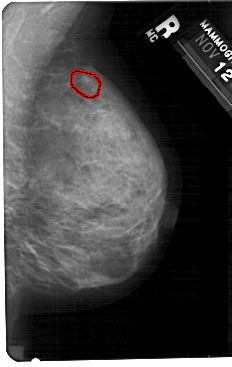

A_1367_1.RIGHT_CC

RIGHT_CC LINES 5491 PIXELS_PER_LINE 3271 BITS_PER_PIXEL 12 RESOLUTION 43.5 OVERLAY

FILE: A_1367_1.RIGHT_CC.OVERLAY

TOTAL_ABNORMALITIES 1

ABNORMALITY 1

LESION_TYPE CALCIFICATION TYPE FINE_LINEAR_BRANCHING DISTRIBUTION CLUSTERED

ASSESSMENT 4

SUBTLETY 3

PATHOLOGY BENIGN

TOTAL_OUTLINES 1

BOUNDARY